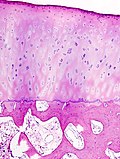

Kod zdravih sinovijalnih zglobova, krajevi kostiju koje formiraju zglob prekriveni su glatkim hrskavičnim tkivom, sastavljenim od kondrocita okruženim vanstaničnim matriksom koji sadrži različite makromolekule, od kojih su najvažnije proteoglikani i kolagen. Hrskavica je tkivo koje ne samo da pokriva površinu kosti unutar zgloba nego i štiti temelj subkondralnog dijela kosti, preraspodjelom velikih opterećenja u zglobu, održavanjem niskog dodirnog opterećenja i smanjenjenjem trenja zglobnih površina. Ona omogućuje kostima da glatko „kližu“ jedna preko druge što omogućuje olakšano kretanje u zglobu i djeluje kao "jastuk" koji apsorbira energiju fizičkih pokreta. Zglobna je čahura obložena sinovijalnom membranom i ispunjena sinovijalnom tekućinom koja štiti i podmazuje zglob. Sinovijalna tekućina se formira ultrafiltracijom plazme, procesom koji se odvija u stanicama sinovijalne membrane (sinoviocitima). Sinovijalne stanice proizvode glavne bjelančevine sinovijalne tekućine, hijaluronsku kiselinu (hialuronat). Sinovijalna tekućina ne samo da sadrži hranljive tvari koje hrane avaskularnu zglobnu hrskavicu, nego svojom viskoznošću apsorbira "udarce sporih pokreta", i daje zglobnoj hrskavici potrebnu elastičnost da može apsorbirati "udare brzih pokreta".

Patološka anatomija

Artroza je bolest koštano-mišićno-zglobnog sustava nastala uslijed trošenja hrskavice zbog prirodnog starenja, prethodnih oštećenja zglobova, te brojnih drugih etioloških faktora. Artroza predstavlja kroničnu degenerativnu promjenu jednog ili više zglobova, okarakteriziranu oštećenjem hrskavice koja prekriva zglobne površine i sekundarnim promjenama kosti koja leži ispod nje. Za razliku od drugih oblika artritisa (postoji oko 100 različitih vrsta), artroza nema utjecaja na unutarnje organe.

Kod artroze se hrskavica troši, povećavajući tako uzajamno trenje kostiju koje tvore zglob. To uzrokuje bol i oticanje, kao i gubitak pokretljivosti zgloba. Tijekom vremena, započinje prekomjerno izrastanje kosti duž zglobnog ruba kojeg nazivamo koštanim izraslinama ili osteofitima. Oni mogu pridonijeti gubitku pokreta u zglobu i povećanju osjećaja boli. Ove se izrasline mogu čak i slomiti i zaglaviti u zglobnom prostoru, što prouzrokuje još jače bolove i oštećenja.